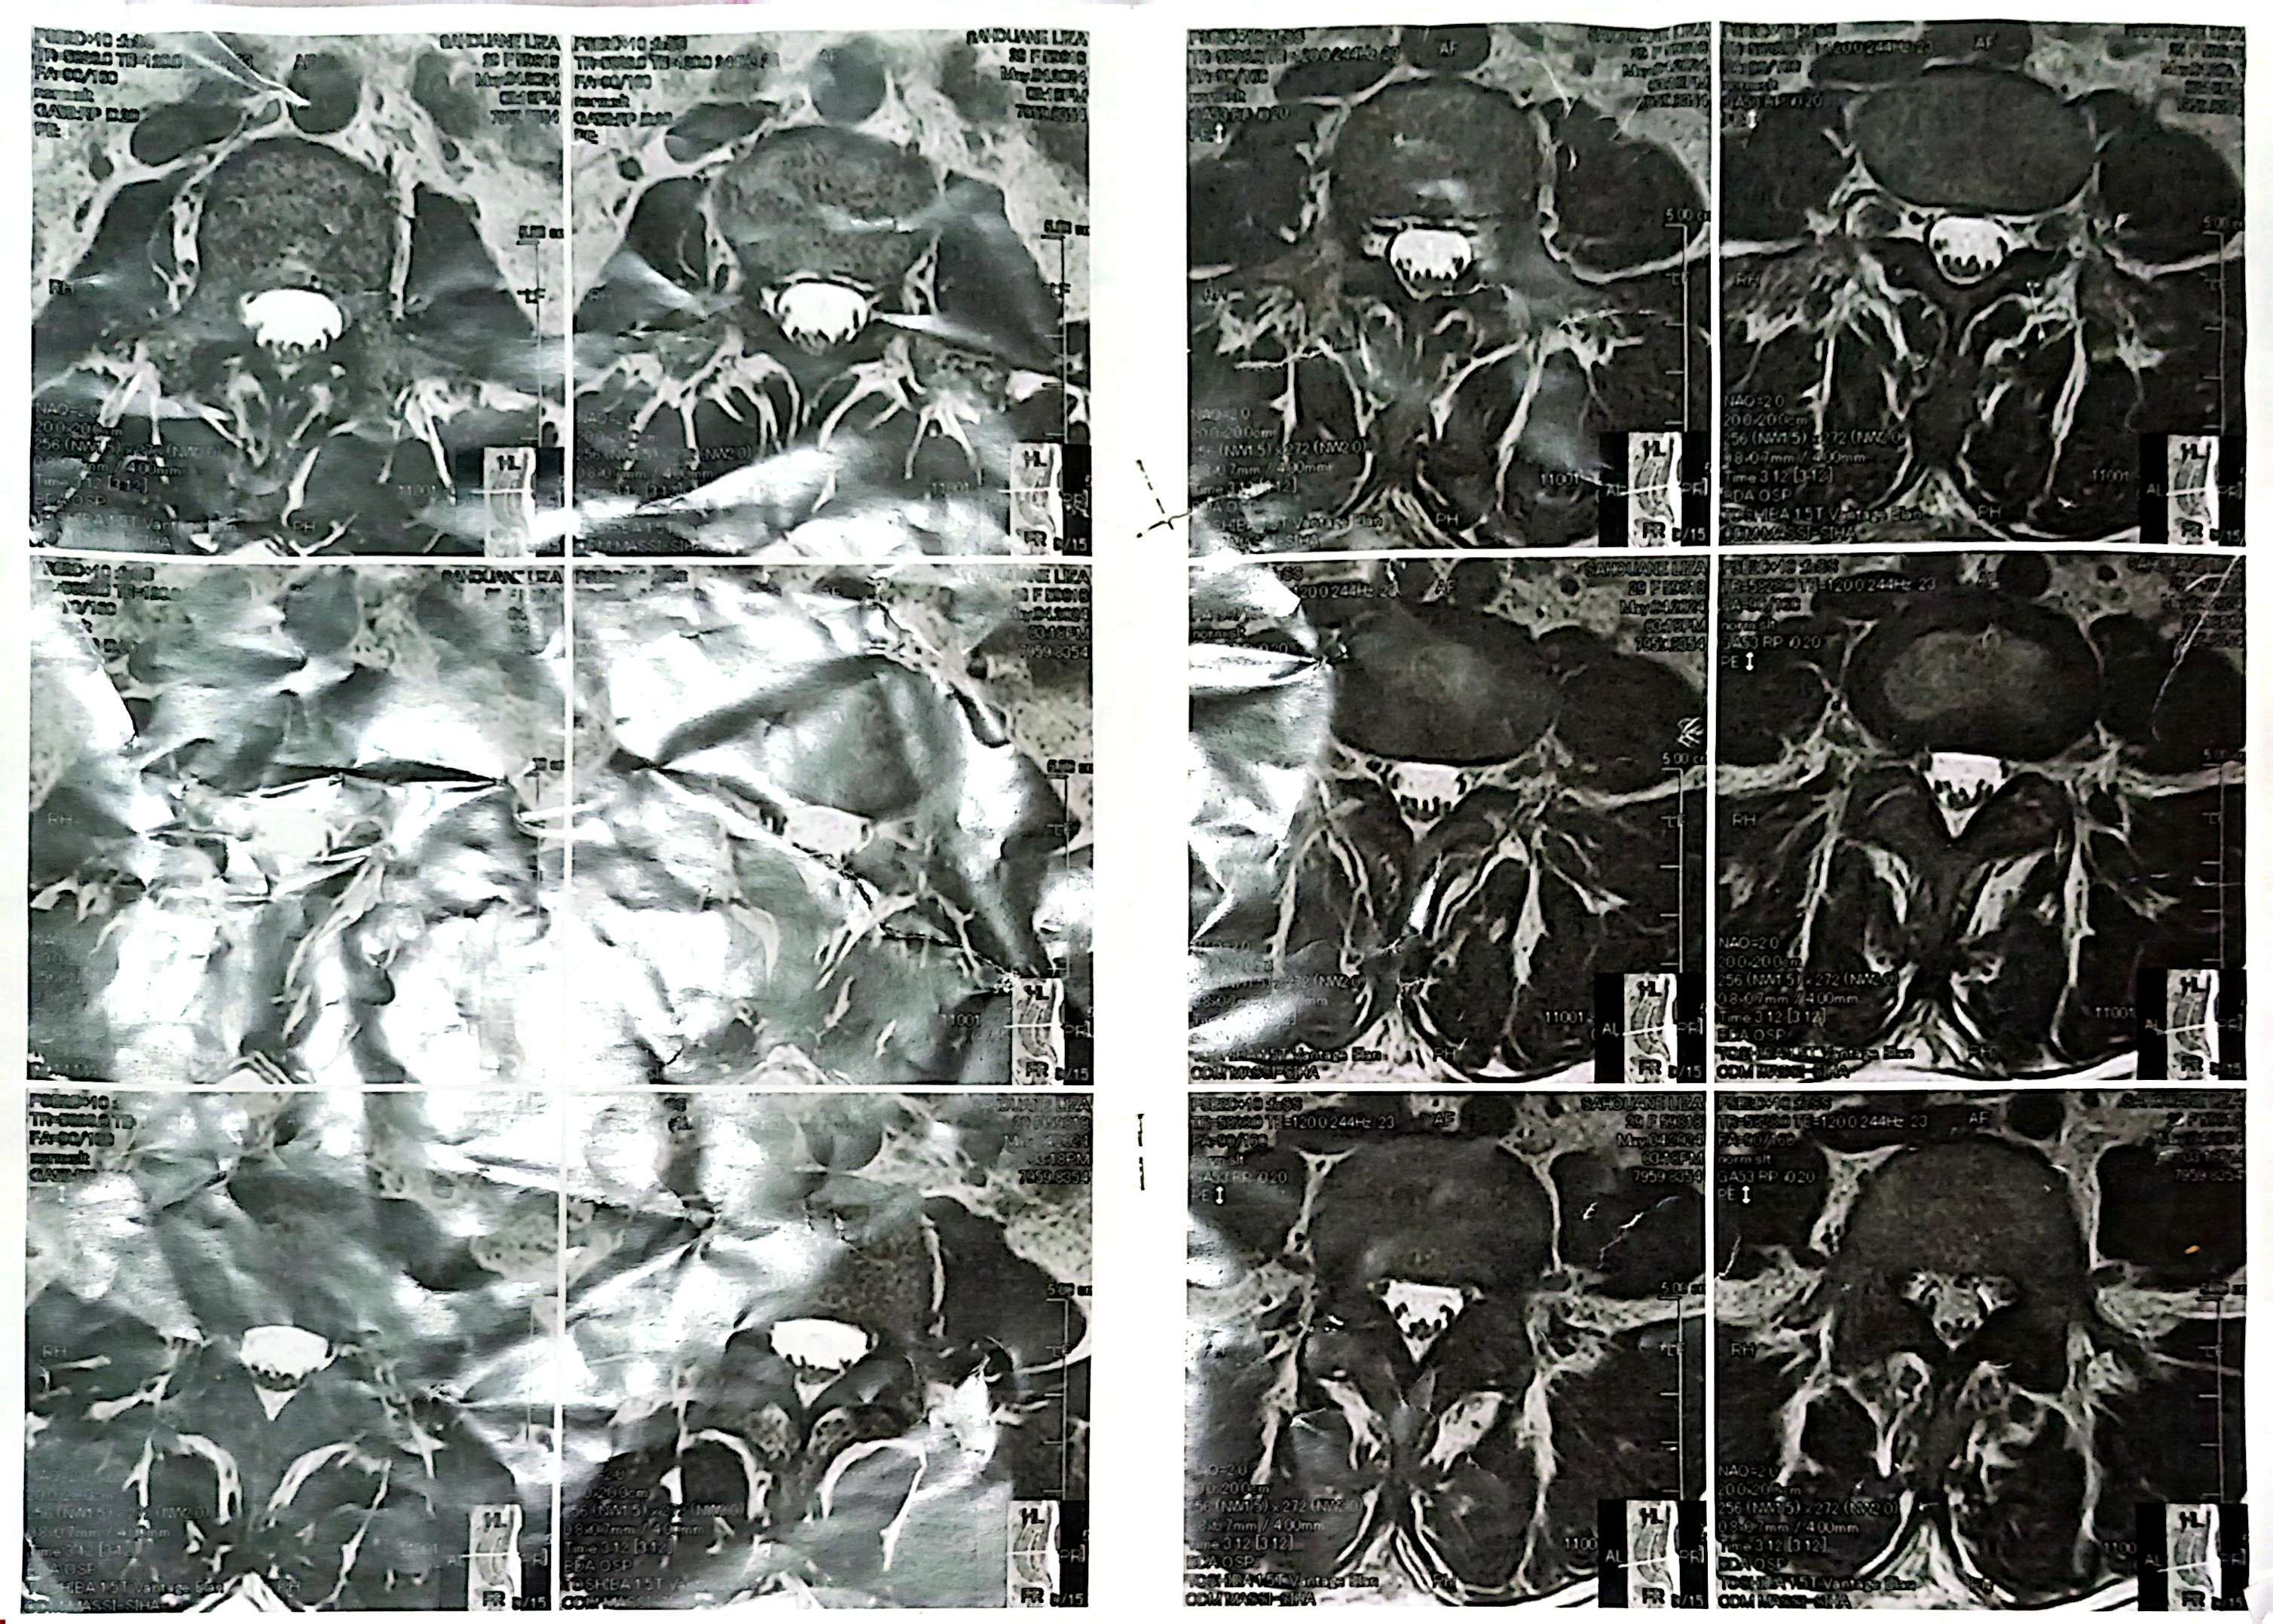

🤲 Je souffre d’une hernie discale L5-S1 et j’ai besoin d’une opération coûteuse. J’appelle à votre solidarité et à vos bonnes actions (sadaqa jariya). Chaque aide compte, qu’Allah vous récompense

Je m’appelle [Radjef Dalia] je suis une asthmatique je souffre à respirer depuis des années et maintenant je souffre depuis plusieurs mois d’une hernie discale L5-S1 qui me cause de fortes douleurs au dos et à la jambe, m’empêchant de vivre normalement et de travailler.